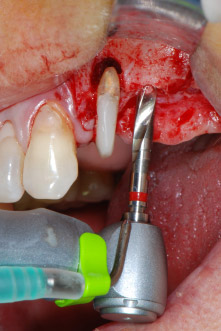

However, we maintained our initial plan to retain both teeth as temporary bridge abutments during the six-months osseointegration period of the implants. At reentry, the situation would have to be reassessed. First, in an attempt to manage the endo-perio problem, the remaining root surface was carefully debrided with piezoelectric equipment (Piezomed, W&H, used with the spatula-shaped insert S1, originally designed for erosion of the lateral sinus wall) (Fig. 4).

Fig. 4: To preserve the tooth as a temporary abutment, the periodontium was debrided with piezoelectric equipment …

buccal apex of tooth 24

Fig 5: ... and the buccal apex of tooth 24 was abraded with the same instrument (apicoectomy).